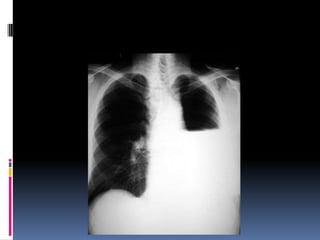

Underpenetrated Film

Hemi diaphragms are obscured

Pulmonary markings more prominent than they actually

Over penetrated Film

 Lung fields darker than

normal—may obscure subtle

pathologies

•   See spine well beyond the

diaphragms

•   Inadequate lung detail

Underpenetrated Film Hemi diaphragmsare obscured Pulmonary markings more prominent than they actually

Over penetrated Film Lung fields darker than normal—may obscure subtle pathologies • See spine well beyond the diaphragms • Inadequate lung detail